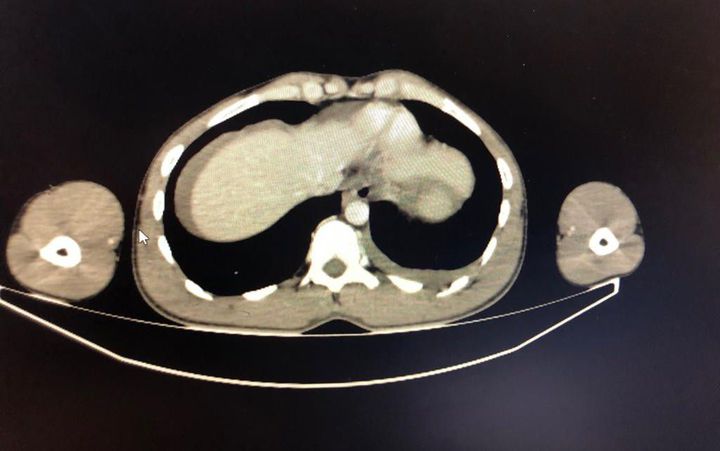

28 years old male patient. left hemothorax due to knife injury. There are also stage 2 spleen injuries.

What are the stages of spleen injury and how you recognise it?

i will share the spleen injury part at my next case.